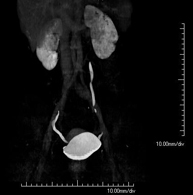

Prueba diagnóstica no invasiva que consiste en el estudio de las arterias ilíacas y la aorta abdominal obteniendo imágenes de alta definición anatómica mediante el empleo de un equipo de TC (Tomografía Computarizada) y de contraste yodado. La calidad de las imágenes permite realizar reconstrucciones en 2D y 3D gracias a estaciones de trabajo especializadas en el estudio arterial. Esta prueba está especialmente indicada como estudio pre-quirúrgico (mapa vascular) antes de intervenciones percutáneas o quirúrgicas de aorta abdominal, como el estudio complementario en pacientes con isquemia de miembros inferiores, etc. - Colonoscopia virtual

Prova diagnòstica no invasiva que consisteix en l'estudi de les artèries ilíaques i l'aorta abdominal amb l'obtenció d'imatges d'alta definició anatòmica mitjançant l'ús d'un equip de TC (Tomografia Computaritzada) i contrast iodat. La qualitat de les imatges permet realitzar reconstruccions en 2D i 3D gràcies a estacions de treball especialitzades en l'estudi arterial. Aquesta prova està especialment indicada com a estudi prequirúrgic (mapa vascular) abans d'intervencions percutànies o quirúrgiques d'aorta abdominal, estudi complementari en pacients amb isquèmia de membres inferiors, etc. - Angio TC arterial d'extremitats inferiors